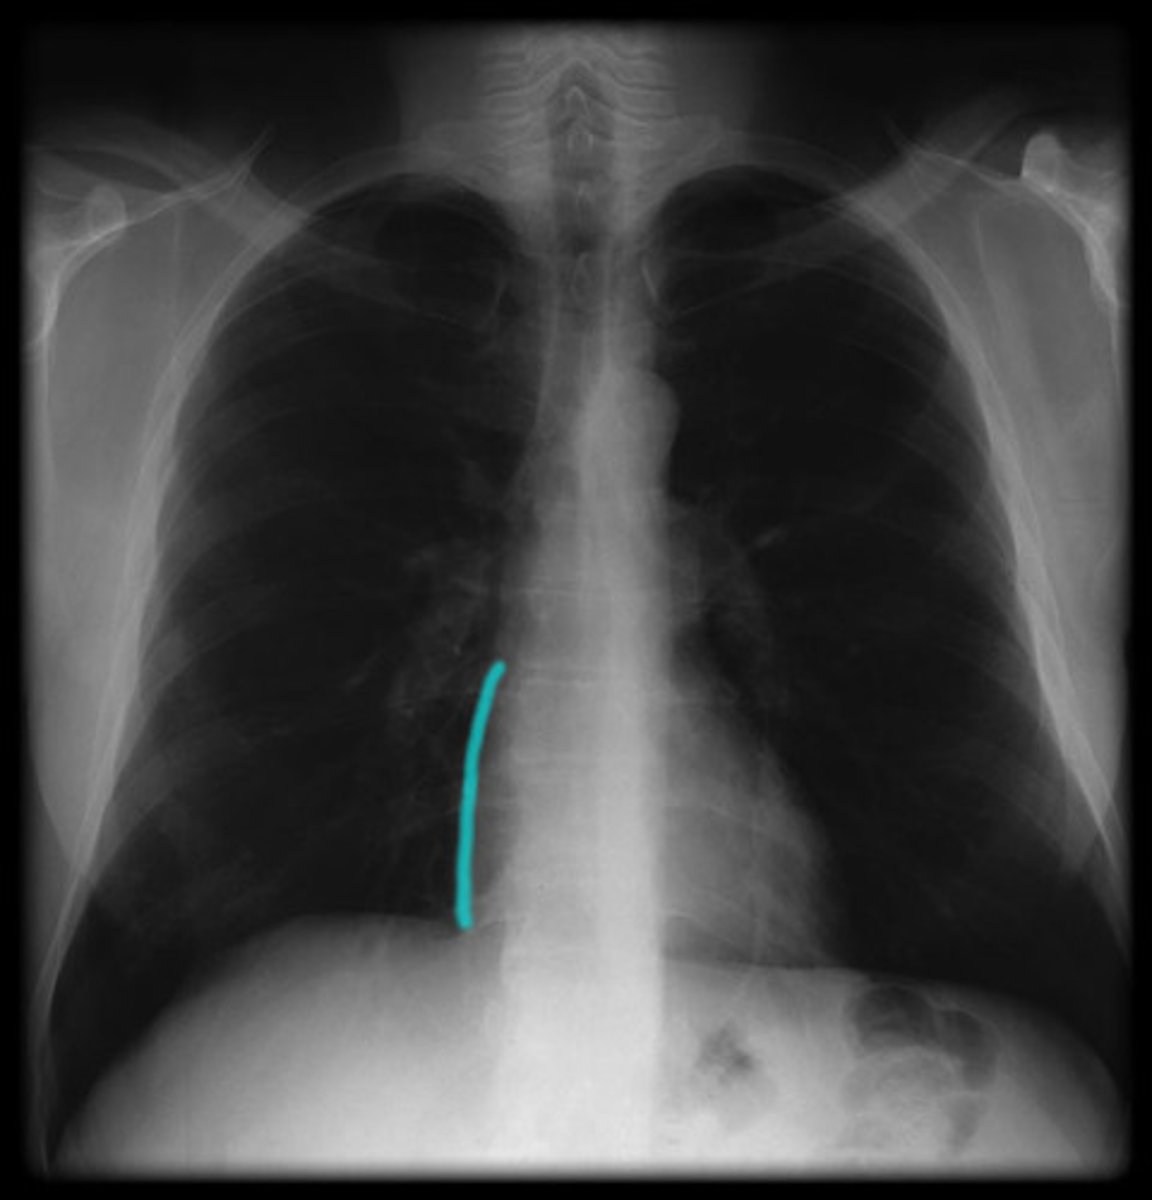

anterior interventricular sulcus

depression. anterior of the heart.